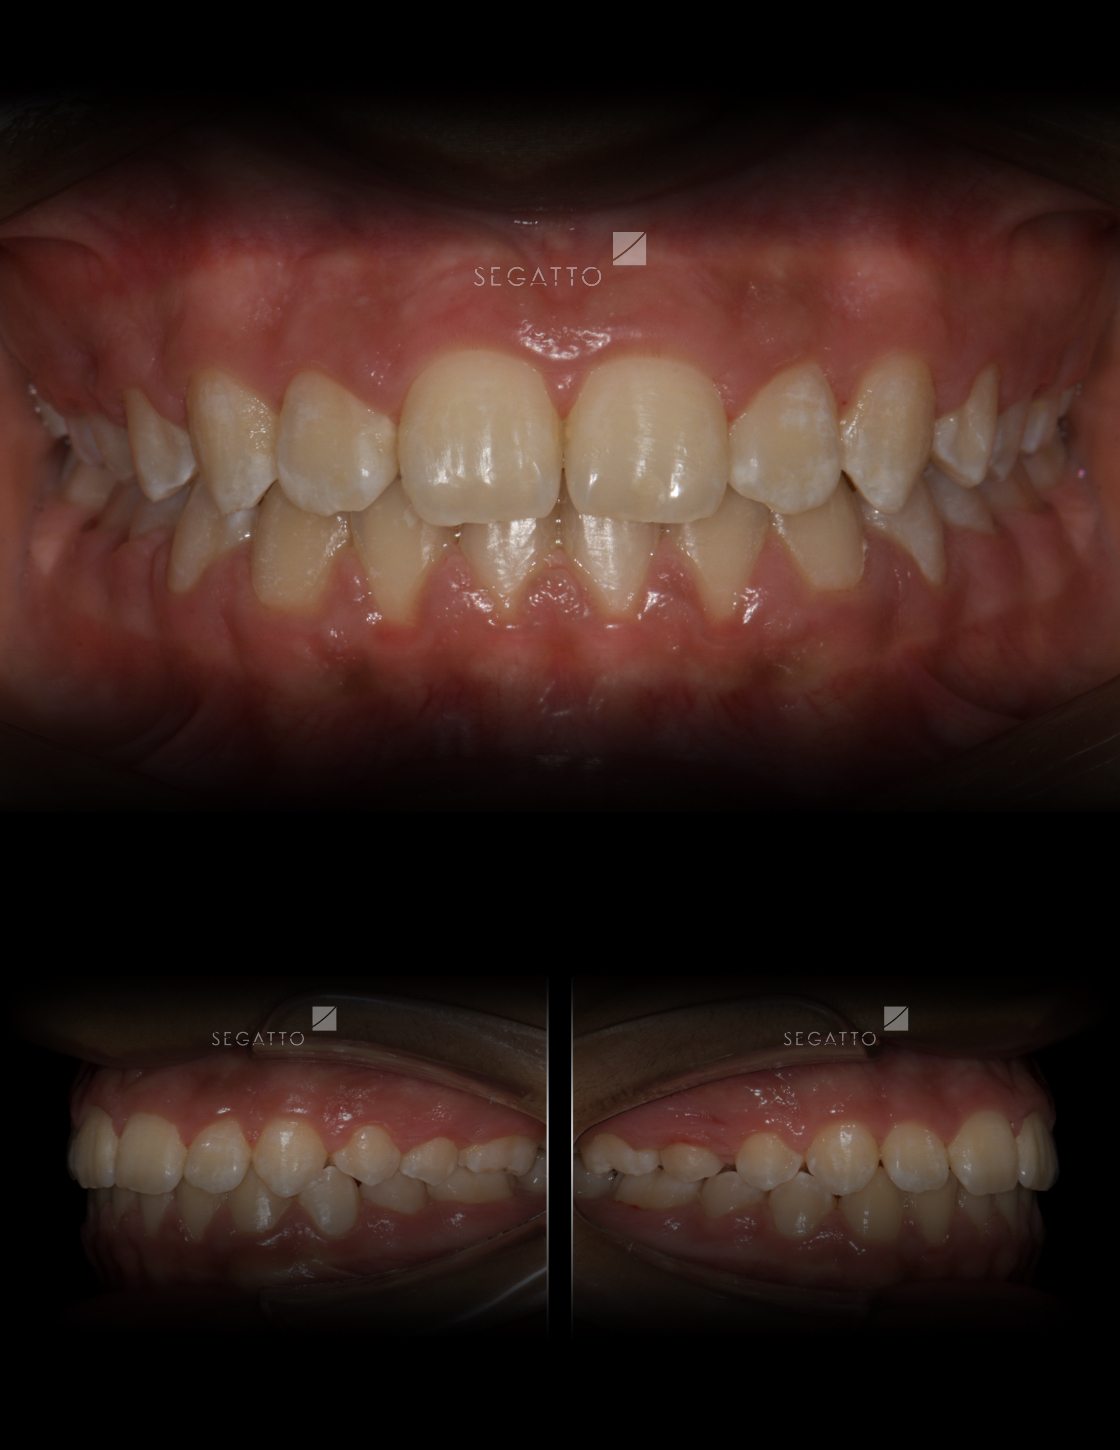

Orthodontics

Cases